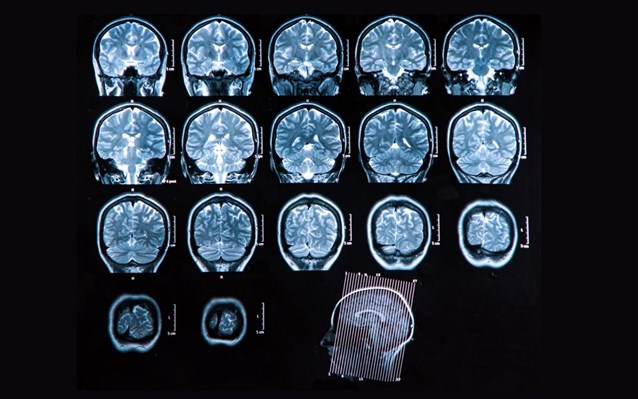

Η σκλήρυνση κατά πλάκας (ΣκΠ) είναι μια ασθένεια του Κεντρικού Νευρικού Συστήματος (ΚΝΣ).